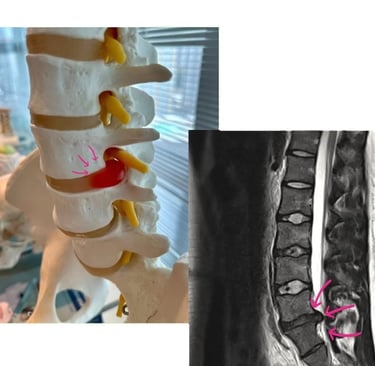

A coluna vertebral lombar suporta grande parte do peso corporal e permite movimentos essenciais do dia a dia. Os discos intervertebrais funcionam como amortecedores entre as vértebras. Quando o anel fibroso externo enfraquece ou se rompe, o núcleo gelatinoso central pode se deslocar (herniar), comprimindo raízes nervosas e gerando inflamação e dor.

Ressonância Magnética (RM): exame de escolha, mostra com precisão a hérnia, o grau de compressão nervosa e o nível afetado. Essencial para planejar procedimentos minimamente invasivos.